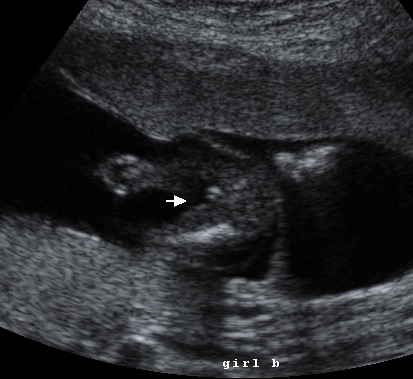

{ our daughter }